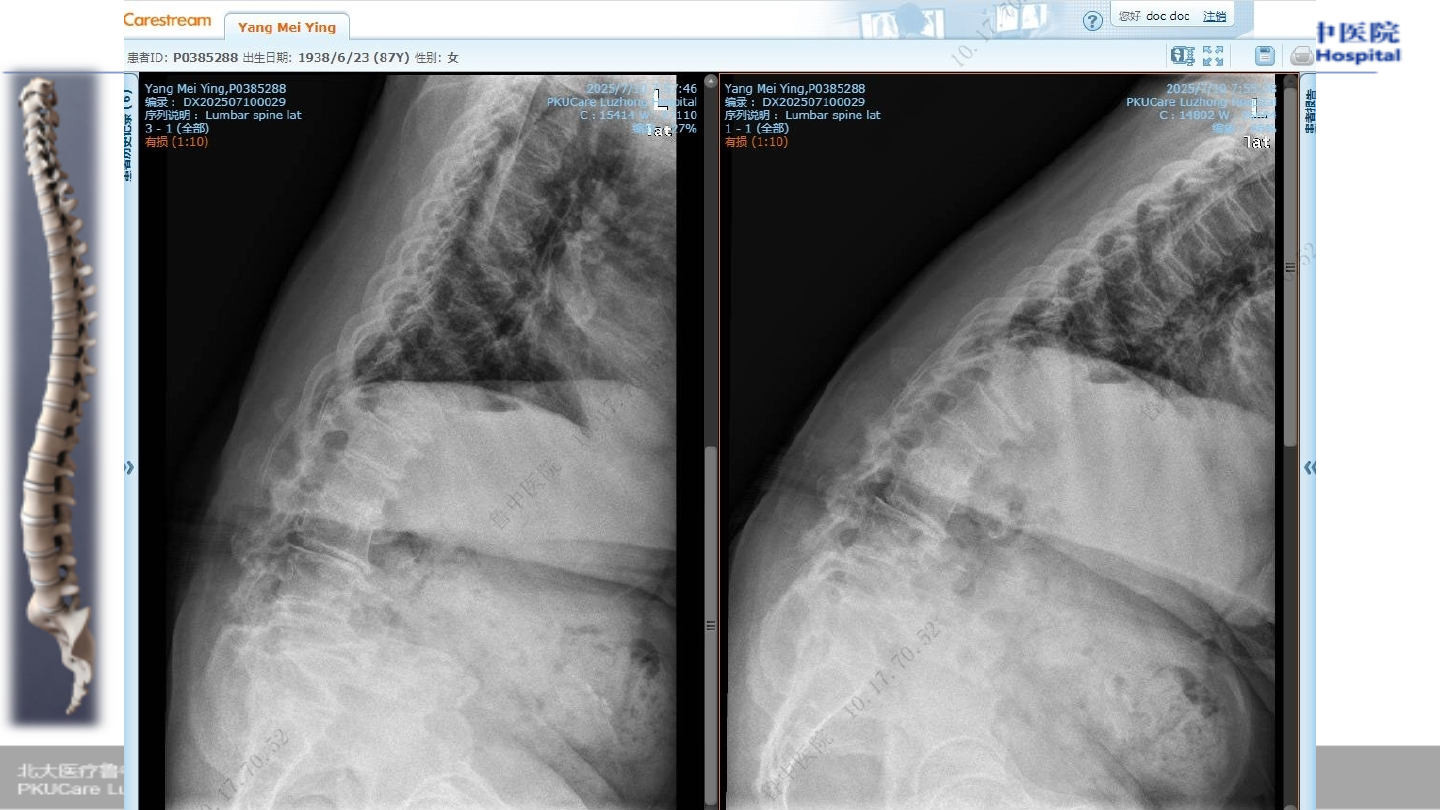

术前

X-ray

查体

Ø

腰椎活动受限,腰段压痛及叩击痛

双下肢小退外侧、足背感觉减退

膝、踝反射存在、病理征阴性

VAS 8

骨密度

T

值:

-3.9